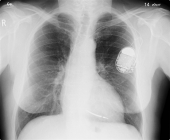

Almost 500K Pacemakers Recalled Due To Hacking Vulnerability

As another sign that the world is becoming interconnected on a terrifying level, nearly 500,000 pacemakers were recalled by the US Food and Drug Administration due to hacking risks. Usually, people perceive hackers as a...